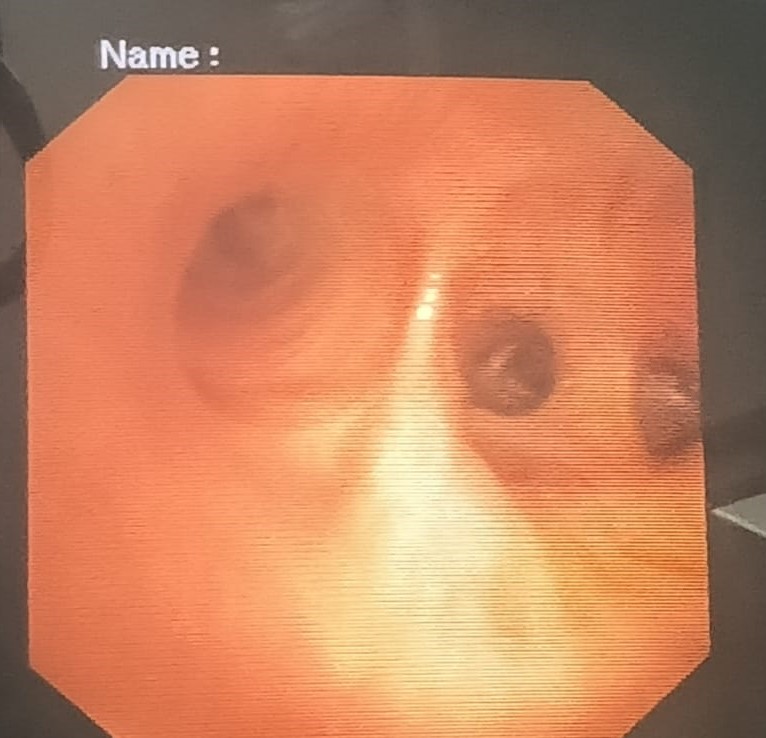

draurtecho Ene 17, 2025 Fibrobroncoscopia diagnostica La broncoscopia es un procedimiento que se realiza para observar el interior de la vía respiratoria, específicamente los bronquios, cuando hay enfermedades pulmonares como tos, flema con sangre etc. Acá muestro imágenes de bronquios. No Comments InNeumología